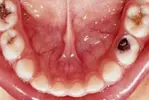

Dental Cavities

Tooth and Gum Diseases